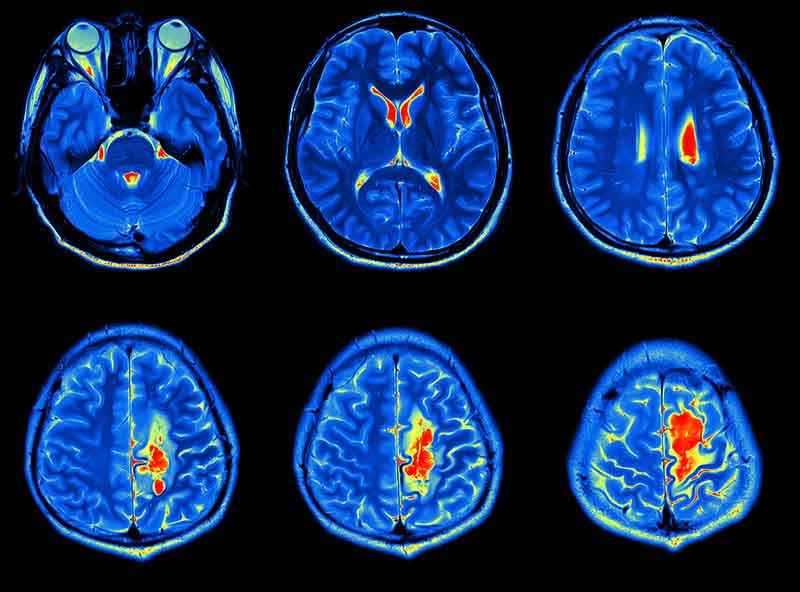

BEYİN TÜMÖRLERİ…

Beyin şişmesine ve irine sebep olabilir. Erken tedavi edilmesi çok önemlidir. Tümör kendisinden oluşmuş ise İlk beyin tümörü olarak söylenir. Kanser akciğere ve beyne göğüs gibi başka yerlere de dağılır. Bu tür tümörler ikincil veya metastatik beyin tümörü olarak söylenir. Diğer kanserlere göre beyin tümörleri oranla az görülür.

Beyin tümörü belirtileri varsa bazı testler yapılması gerekir. Anormal belirtileri tespit etmek için bir kaç tane diyagnostik harekat uygulanır. Uzman doktor tarafından değerlendirilip ve teşhis konulması ve tedavisine başlanır.